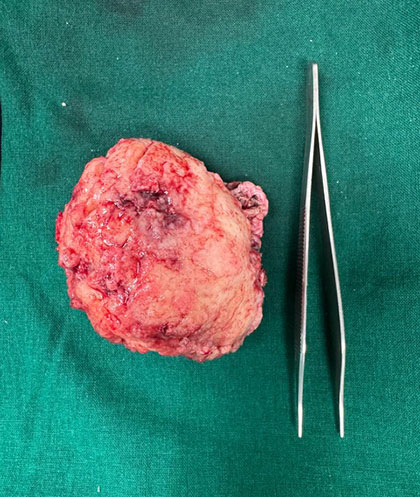

Surgical Highlights